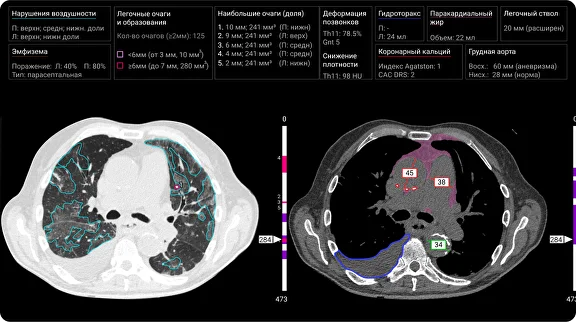

Компьютерная томография (КТ) – один из важнейших методов диагностики в пульмонологии. Она позволяет получить детальное изображение легких и выявить различные патологии. Однако интерпретация КТ-снимков – задача трудоемкая и требующая большого опыта. Здесь на помощь приходит ИИ.

Современные алгоритмы ИИ способны анализировать КТ-снимки с высокой скоростью и точностью, выявляя даже самые незначительные изменения в структуре легких. Они могут автоматически определять наличие очагов воспаления, опухолей, фиброзных изменений и других патологий. Это значительно облегчает работу врачей и позволяет ускорить процесс диагностики.

ИИ может быть использован для количественной оценки фиброза на основе КТ-снимков. Алгоритмы ИИ способны измерять объем и плотность фиброзной ткани, что позволяет врачам отслеживать динамику заболевания и корректировать лечение при необходимости.